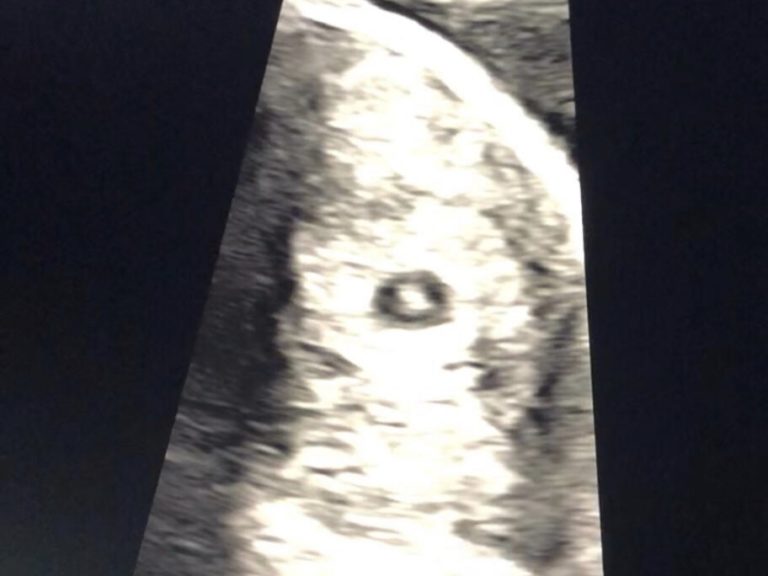

S: 8.10am, and Em messaged to say she was there. Jack and I sat in the lounge with my mum, who is currently staying with us (and wouldn’t leave our sides that morning!). Em tried FaceTime, but her reception was so bad it wasn’t connecting. 2, 3, 4, and 5 minutes felt like a lifetime. 7 minutes later, we get a photo on our group WhatsApp. It’s a scan photo, but we can’t figure out what it shows. Then she calls…

E: Bloody technology! When I couldn’t connect to them, I felt terrible – I wanted them to be there with me so much! But in the end we all agreed it was for the best, as I could record the whole scan instead. So I recorded the HEARTBEAT flickering away… I can’t tell you how proud and excited I felt at that moment. I think I did a mini fist punch on the bed at the thought of reaching the most significant milestone yet. This was starting to feel like a marathon and we had just gotten up and over the biggest hill in my opinion!

S: THERE’S A HEARTBEAT! These are the 3 words we’ve longed to hear for over 5 years. I think I scream. I can’t remember. There were definitely a fair few seconds when I didn’t breathe properly. Mum was up saying ‘YES’ and burst into tears, Jack had a grin on his face I don’t see too often and his eyes lit up. I just kept saying ‘Are you joking Em, are you joking!’. I was just so thankful in that moment. Em had gone into that scan by herself like the trooper she is and we had at that point got further than we had ever done before. A bloody heartbeat! Seriously.

S: Em sent us the video she had taken of the scan. When the nurse says ‘There’s a baby with a heartbeat. Can you see the flicker’ my own heart skipped a beat. I kept replaying it repeatedly just to ensure I wasn’t dreaming. It’s a video we will all be treasured forever. It was our baby with a heartbeat.

S: We were under no illusion that it was still such early days and we couldn’t think too far past that moment as we know hopes get raised and then come crashing down in pregnancy, and we were still only 6 weeks 2 days. However, that evening we shared a bottle of Prosecco and celebrated this small but very BIG step for us. Now we needed to wait 2 weeks for the next scan, which I had booked for when Em got to Glasgow. 2 whole weeks to try and not turn to google again. Come on, Baby Smith hang in there ❤️